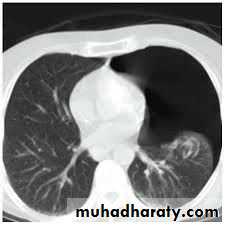

Fall from the 2nd floor